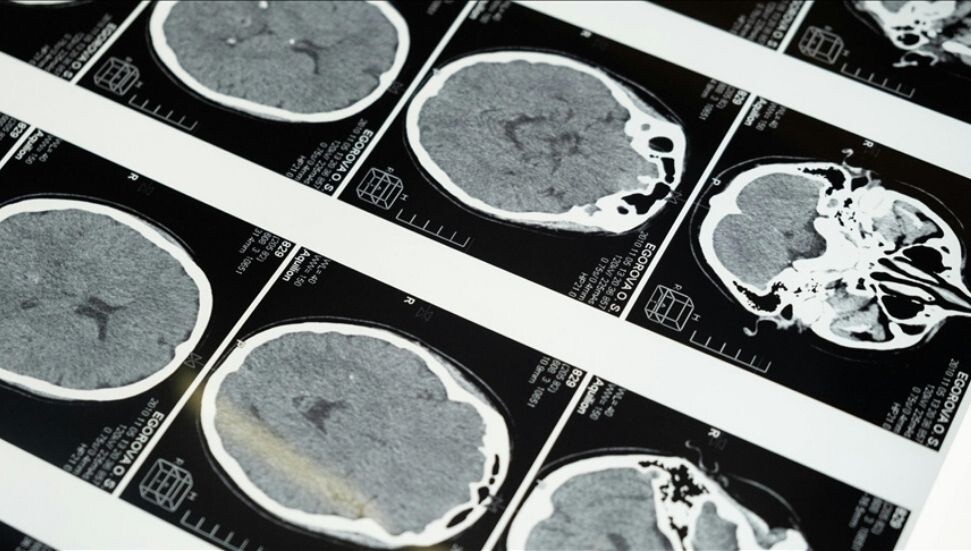

Bulguları hakemli dergi Translational Psychiatry'de 14 Temmuz Pazartesi günü yayımlanan çalışmayı yürüten ekip, şizofreni, bipolar bozukluk veya majör depresyonu olan kişilerin ölümden sonra beyinlerinden alınan koroid pleksus örneklerini, sağlıklı bireylerin beyinlerinden alınanlarla karşılaştırdı.

Koroid pleksus, sıvı dolu boşlukların yani ventriküllerin zarını oluşturan ve özellikle beyni ve omuriliği koruyan beyin omurilik sıvısını üreten hücre topluluğunu ifade ediyor. Daha önceki çalışmalarda beyin içinde virüs keşfedilmediği için virüslerin bulaştığı bilinen bu bölgeye odaklandılar.

Araştırmacılar 3 binden fazla hücreyi saptayabilen bir teknolojiyi kullanarak şizofreni veya bipolar bozukluktan muzdarip kişilerden alınan örneklerde daha fazla virüs tespit etti. Ancak sadece bu kişilerin beyin zarında Hepatit C vardı.